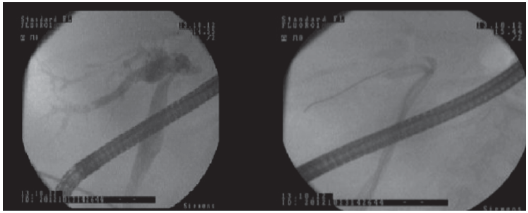

Doppler ultrasonography allowed diagnoses of biliary dilatation in 12 LT patients with bile stones. Five patients with normal ultrasonography findings had intrahepatic dilatation and filling defect in the major bile duct diagnosed by magnetic resonance cholangiopancreatography, and one patient was diagnosed by interventional radiology. Nine patients with bile stones had endoscopic retrograde cholangiopancreatography first, with 5 of these patients having a successful procedure (Figure 1). The remaining 4 patients required bile duct casts and stones cleared by percutaneous transhepatic cholangiography (basket catheter or balloon dilatations) (Figure 2). The percutaneous transhepatic cholangiography procedures were repeated in 10 patients every 3 weeks. With these treatments, all patients recovered, showing normal radiologic, clinical, and laboratory findings. One patient lost graft function as a result of recurrent biliary complications and cholangitis. No patients died as a result of bile stones.

Figure 2. Bile Stones After Liver Transplant Treated With Percutaneous Transhepatic Procedure